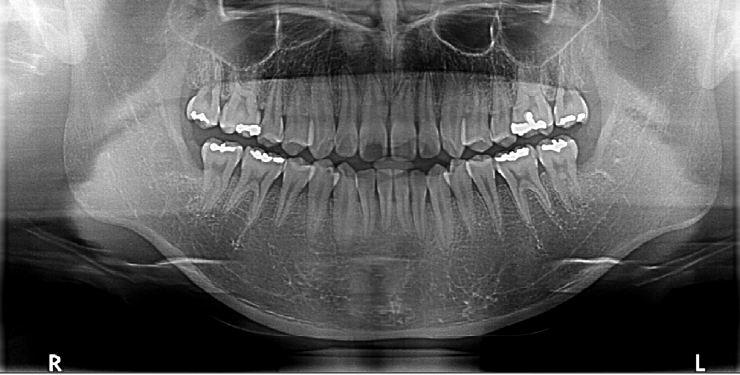

Figure 1.

Preoperative panoramic radiograph showing bilaterally impacted mandibular third molars without apparent bony pathology.